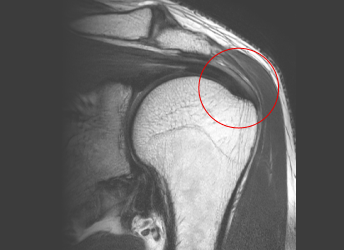

회전근개파열 환자의 MRI